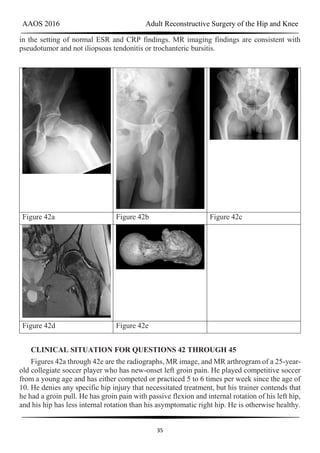

Figure 42a Figure 42b Figure 42c

Figure 42d Figure 42e

CLINICAL SITUATION FOR QUESTIONS 42 THROUGH 45

Figures 42a through 42e are the radiographs, MR image, and MR arthrogram of a 25-year-

old collegiate soccer player who has new-onset left groin pain. He played competitive soccer

from a young age and has either competed or practiced 5 to 6 times per week since the age of

10. He denies any specific hip injury that necessitated treatment, but his trainer contends that

he had a groin pull. He has groin pain with passive flexion and internal rotation of his left hip,

and his hip has less internal rotation than his asymptomatic right hip. He is otherwise healthy.